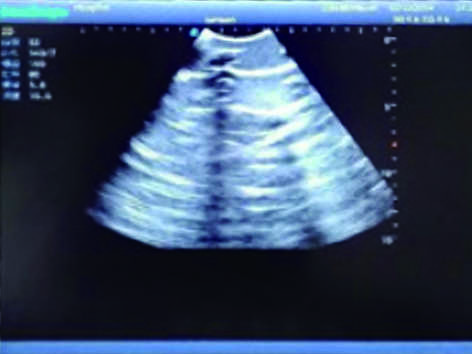

Pneumothorax & Thoracic Closed Drainage Ultrasound Training Model

Model TYE1566

It is a model covering up from the neck to the umbilicus with body surface markers such as ribs, intercostal space, left and right intercostal arches, armpits and nipples.

2)  Made of high molecular polymer ultrasound material, close to the real skin. It can conduct ultrasound-guided puncture exercises with various clinical models of real ultrasound machines.

3)  Showing clear and real images of the tissues and organs (including muscle and connective tissue, air-containing lung tissue, pleural structure)